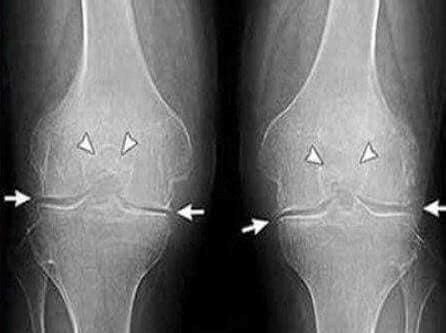

Rendgen sa očiglednim znacima artroze

- Dan 35: Otišao sam doktoru i napravio rendgenski snimak. Nema tragova artroze! Hrskavica u zglobovima kao kod 20-godišnjeg klinca.

Doktorka je rekla da je prethodni rendgen najverovatnije imao defekt, pa je dijagnoza artroze pogrešna.